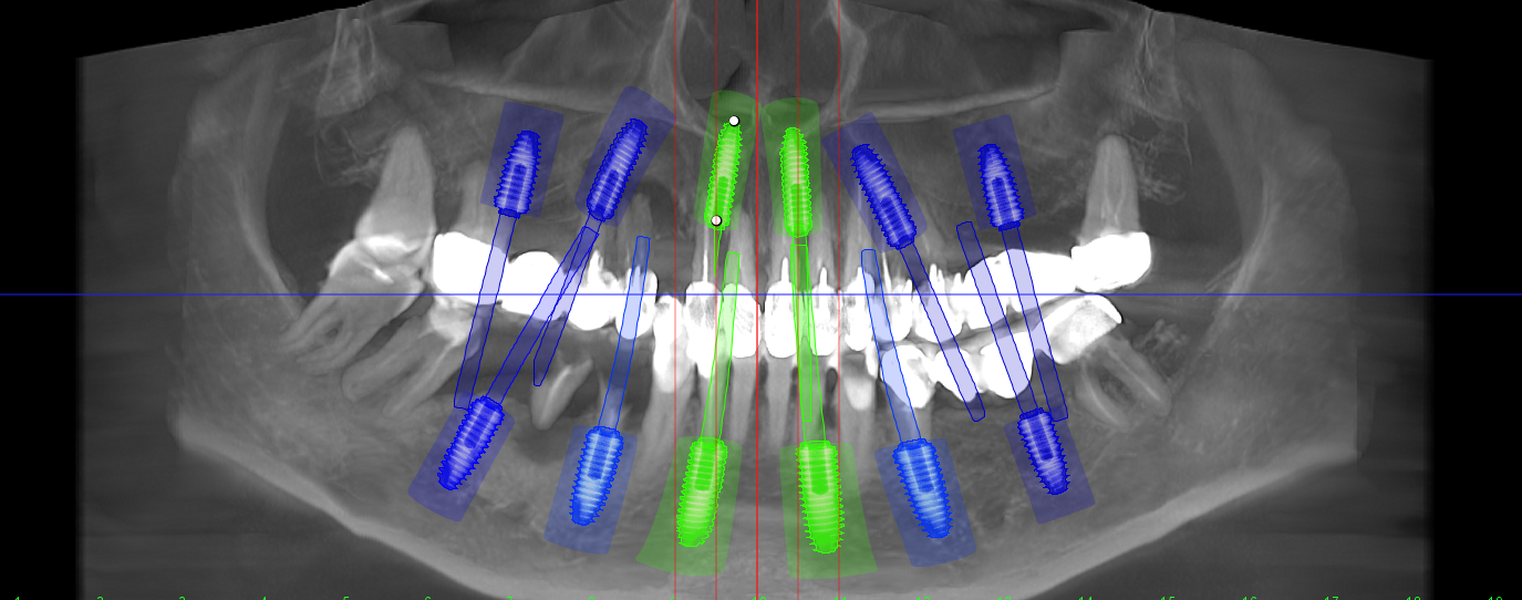

- Investigație imagistică completă, ideal CBCT (computer tomografie);

- Consult clinic detaliat și obiectiv;

- Planificare computerizată a intervenției, inclusiv realizarea și utilizarea ghidului chirurgical, dacă este necesar;

Caz 1

Caz 2